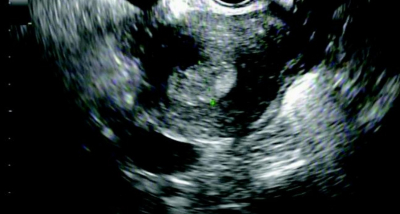

身長 155 cm、体重86 kg。腟鏡診で少量の出血を認める。子宮頸部には肉眼的異常を認めない。妊娠反応は陰性。経腟超音波検査で両側卵巣の多囊胞性腫大を認める。子宮の経腟超音波像を別に示す。